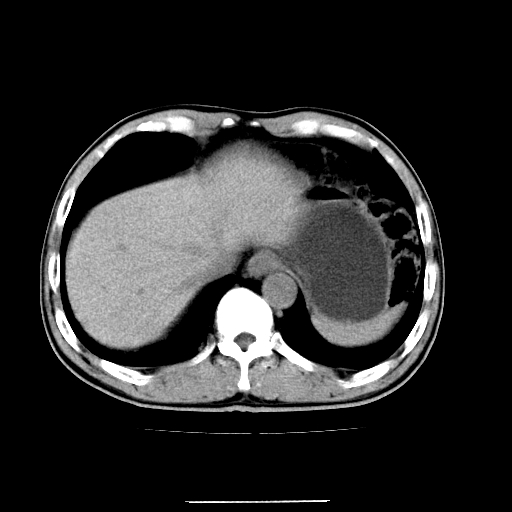

患者男,64岁,胃癌术后三个月,无明显不适。请讨论一下胰头前方小圆形低密度影为淋巴结还是肠管?

肠管吧.另外右肾见盂旁囊肿.

肠管.右肾见盂旁囊肿.

典型的无明显强化改变的淋巴结。

增强第6幅图上有气液平相通,是肠管,右肾低密度灶形态不规则似有壁结节,不除外转移.

胰头低密度影考虑是肠管

应该考虑是肠管,理由1、平扫和增强对比,形态和内部的密度有明显改变。2、增强图片可见明显气液平面。

是肠管影,肠壁有强化。